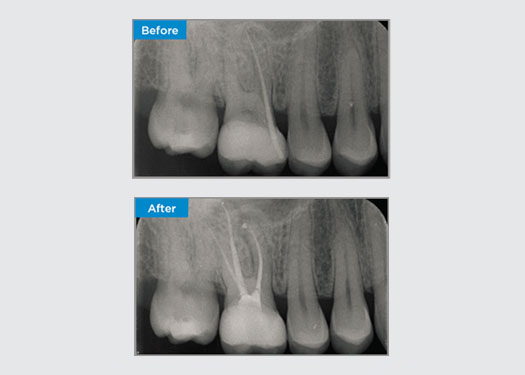

El paciente presentó pulpitis irreversible en la pieza dental 46. A partir de la radiografía preoperatoria, la pieza dental 46 se presenta con una raíz distal adicional (morfología dental Radix Entromolaris). Una escaneo CBCT ha confirmado la presencia de raíz distolingual con curvatura grave de la raíz. Una cuidadosa selección de limas es fundamental para esta raíz distobucal delicada.

Dr. Jack Lin, endodoncista, Sídney, NSW Australia

En esta situación, la preservación de la estructura del diente/raíz es esencial para reducir el riesgo de reborde, transporte, cierre, perforación y fractura de la raíz. La selección de casos, el diagnóstico y la planificación previa al tratamiento son importantes. La selección de limas de endodoncia con flexibilidad, eficiencia y respeto por la anatomía de la raíz natural es fundamental.